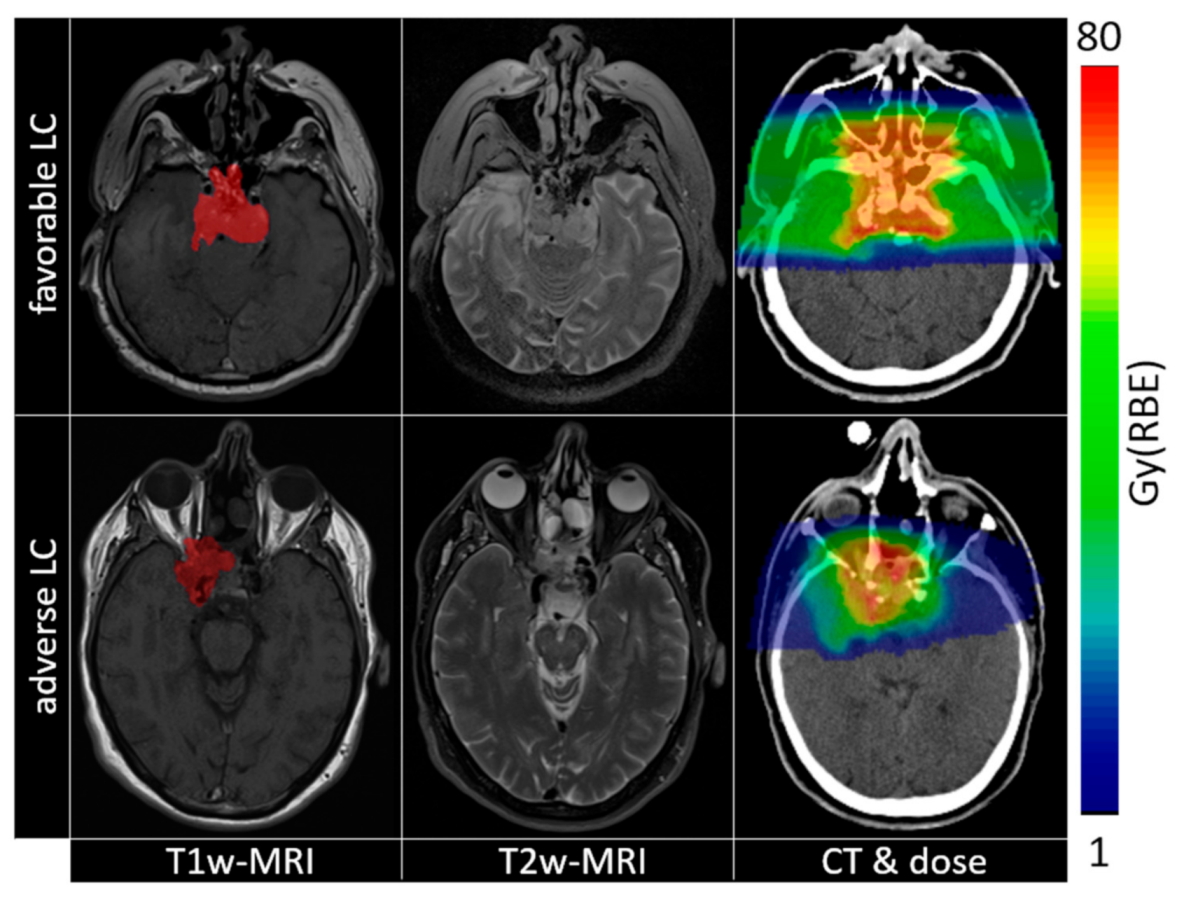

Figure 3.

Imaging (from left to right: T1w-MRI, T2w-MRI, CT) and dose maps (overlaid to CT) for patients with opposite local control evaluation (top row favourable LC, bottom row adverse LC). Tumour contours are shown as red overlays on T1w-MRI images.

4.2. Data Preparation